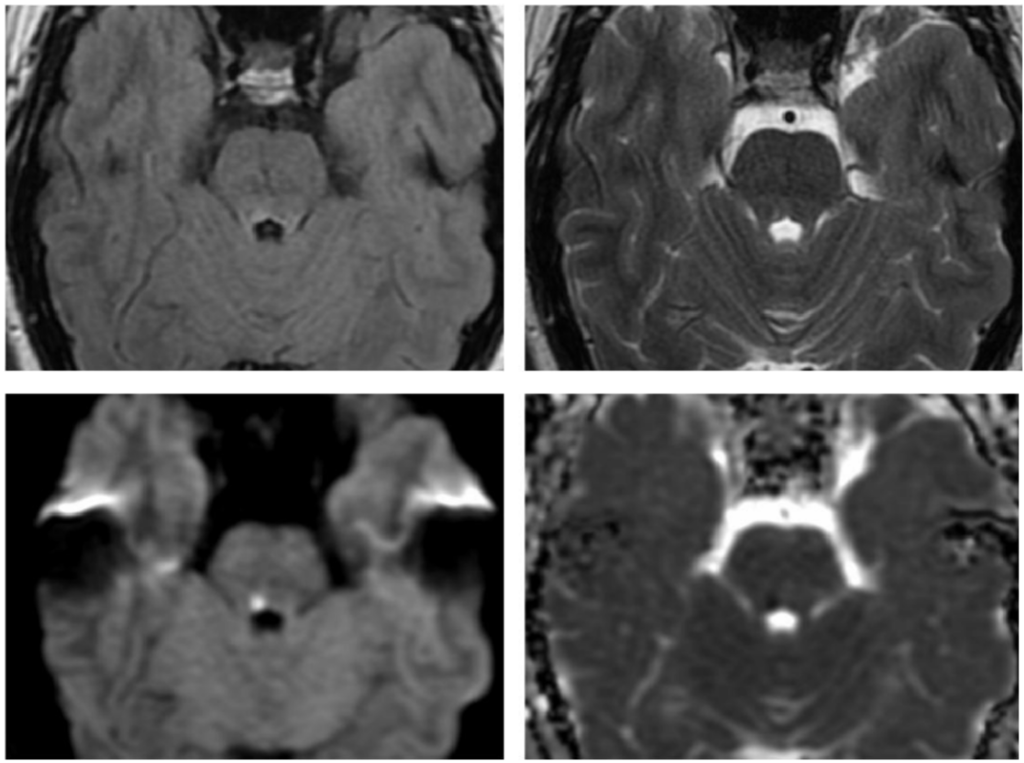

El presente caso ilustra un infarto isquémico del mesencéfalo medial, con una distribución paramediana bilateral y predominio a nivel del tegmento, acompañado de extensión caudal limitada hacia la unión pontomesencefálica. Este patrón topográfico, identificado mediante la combinación de secuencias de difusión y mapas ADC, es característico de la afectación de las ramas perforantes paramedianas del segmento distal de la arteria basilar y/o del segmento proximal de la arteria cerebral posterior, responsables de la irrigación del mesencéfalo medial, y ha sido descrito en infartos mesencefálicos mediales bilaterales dependientes de estas ramas perforantes.(5, 16)

En términos topográficos, la bilateralidad y simetría de la lesión constituyen un elemento clave para su correcta interpretación. A diferencia de los síndromes mesencefálicos alternos clásicos, como los síndromes de Weber o Benedikt, en los que el compromiso es típicamente unilateral y se extiende hacia los pedúnculos cerebrales, en este caso la lesión se encuentra confinada al tegmento medial, sin afectación significativa de las estructuras laterales, patrón previamente reportado en series imagenológicas de infartos mesencefálicos mediales.(5, 16) Este hallazgo permite descartar un patrón peduncular y refuerza el diagnóstico de un infarto mesencefálico medial.

La extensión rostro-caudal observada, con compromiso adicional del puente rostral, no debe interpretarse como la coexistencia de lesiones independientes, sino como la expresión de un territorio vascular continuo, fenómeno descrito en infartos dependientes de perforantes paramedianas largas.(17, 18) En este contexto, el análisis del eje rostro-caudal resulta tan relevante como la evaluación dorsoventral, en especial en lesiones localizadas en zonas de transición anatómica.

En este caso, la lesión se localiza predominantemente a nivel del mesencéfalo medial, con una distribución paramediana bilateral y extensión caudal limitada hacia la unión pontomesencefálica. Este patrón topográfico permite integrar los hallazgos imagenológicos dentro de un infarto mesencefálico medial y diferenciarlos de otros síndromes mesencefálicos clásicos con compromiso lateral o peduncular.(5)